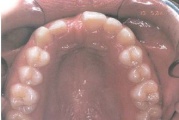

Lutipudelikaariese kahjustused

Lutipudelikaaries